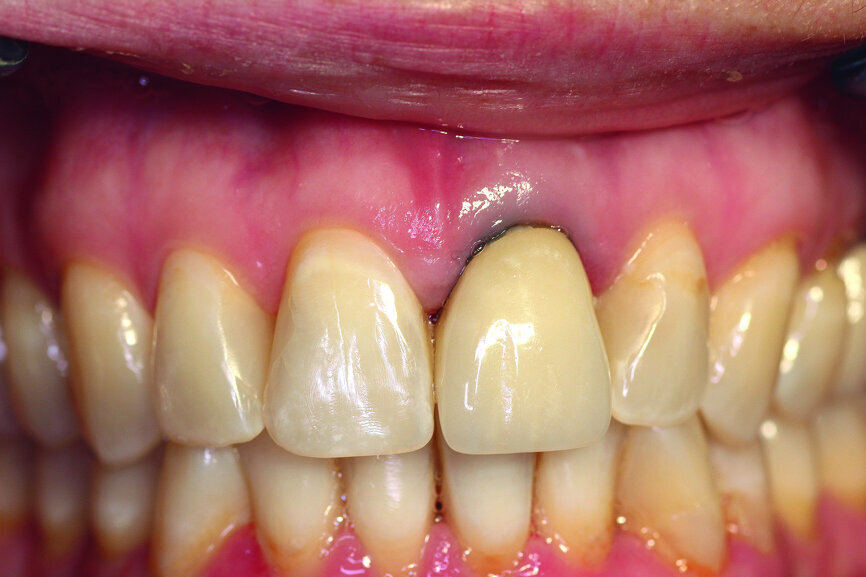

A 40-year-old female patient presented to our dental surgery with an irreparable tooth #21 (Fig. 1). The periapical radiograph revealed an approximately 7 mm periapical translucency with widening of the periodontal ligament in the upper third of the root (Fig. 2). Owing to the clinical conditions (high smile line and good oral hygiene), we decided to use a two-piece ceramic implant, ZERAMEX XT (Dentalpoint).

Fig. 1: Initial clinical situation.